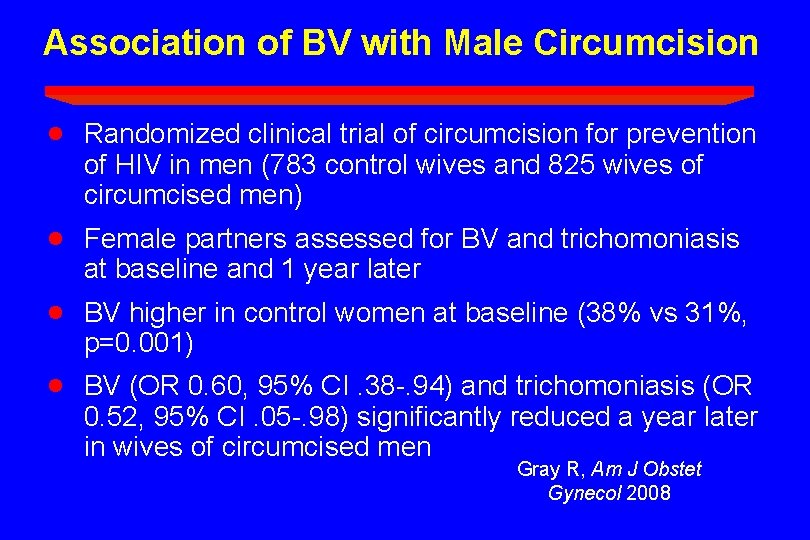

Association of BV with Male Circumcision · Randomized clinical trial of circumcision for prevention of HIV in men (783 control wives and 825 wives of circumcised men) · Female partners assessed for BV and trichomoniasis at baseline and 1 year later · BV higher in control women at baseline (38% vs 31%, p=0. 001) · BV (OR 0. 60, 95% CI. 38 -. 94) and trichomoniasis (OR 0. 52, 95% CI. 05 -. 98) significantly reduced a year later in wives of circumcised men Gray R, Am J Obstet Gynecol 2008